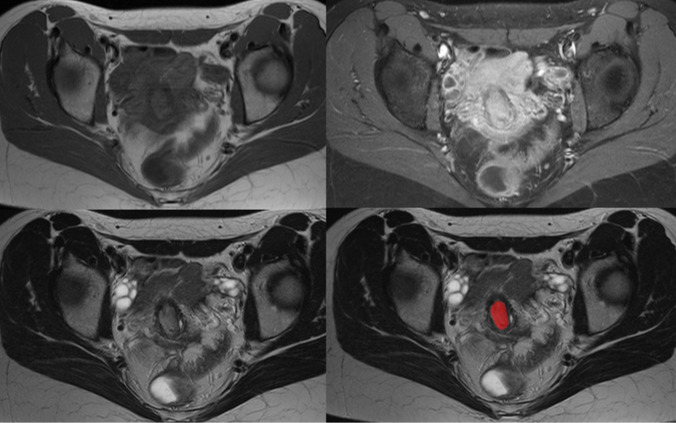

Purpose: The complex interactions of the tumor micromilieu could be reflected by magnetic resonance imaging (MRI) when analyzed with the radiomics approach. For several tumor entities, it has been shown that radiomics derived from MRI can reflect important characteristics of the tumors. The present study investigated the association radiomics derived from MRI images and histopathological features in uterine cervical cancer.

Methods: The MRI before any treatment was used to extract the radiomics features of T1- and T2-weighted images. The biopsy specimens were stained for Ki 67, e-cadherin, vimentin, programmed-death ligand 1, and tumor-infiltrating lymphocytes (TIL, all CD45 positive cells). Tumor-stroma ratio (TSR) was calculated on routine H&E specimen. Spearman's correlation analysis and discrimination analyses were performed as statistical analyses.